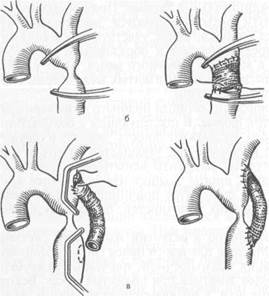

Хирургические методы лечения. Классические реконструктивные оперативные вмешательства можно разделить на четыре группы: I) эндартерэктомия — операция с удалением пораженной интимы; 2) шунтирование; 3) протезирование; 4) эндолюминальная дилатация, дилатация с установкой стента. Больным с сегментарными окклюзиями артерий, не превышающими по протяженности 7—9 см, показана эндартерэктомия. Операция заключается в артериотомии и удалении измененной интимы вместе с атероскле-ротическими бляшками и тромбом. Операцию можно выполнить как закрытым (из поперечного разреза артерии), так и открытым способом (рис. 18.2; 18.3). При закрытом способе имеется опасность повреждения инструментом наружных слоев артериальной стенки. Кроме того, после удаления интимы в просвете сосуда могут остаться ее обрывки, благоприятствующие развитию тромбоза. Вот почему предпочтение следует отдавать открытой эндартерэктомии, при которой производят продольную артериотомию над облитерированным участком артерии и под контролем зрения удаляют измененную интиму с тромбом. Для предупреждения сужения просвет рассеченной артерии может быть расширен путем вшивания заплаты из стенки подкожной вены. При операциях на артериях крупного калибра испольуют заплаты из синтетических тканей (политетрафторэтилен). Некоторые хирурги применяют ультразвуковую эндартерэктомию.

Эндартерэктомия противопоказана при значительной длине окклюзии, выраженном кальцинозе сосудов. В этих случаях показано шунтирование или протезирование (резекция пораженного участка артерии с замещением его синтетическим или биологическим протезом).

Рис. 18.3. Открытая эндартерэктомия.